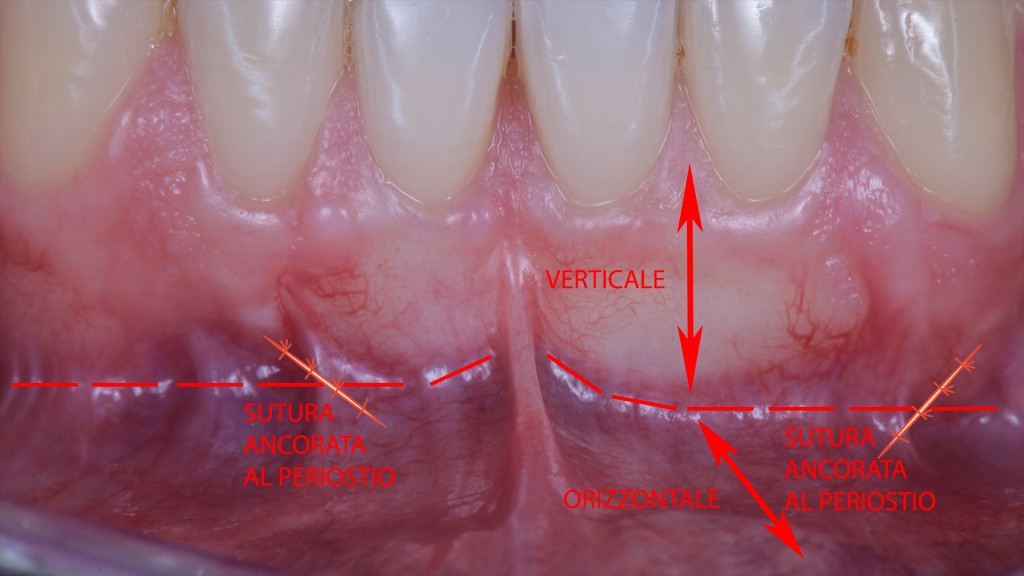

Per fare questo basta iniziare a suturare proprio in quel punto, prima su uno scarico verticale e poi sull’altro, ancorando i punti al periostio del tessuto non mobilizzato laterale. Ovviamente mantenedo il lembo nella posizione finale con le pinzette.